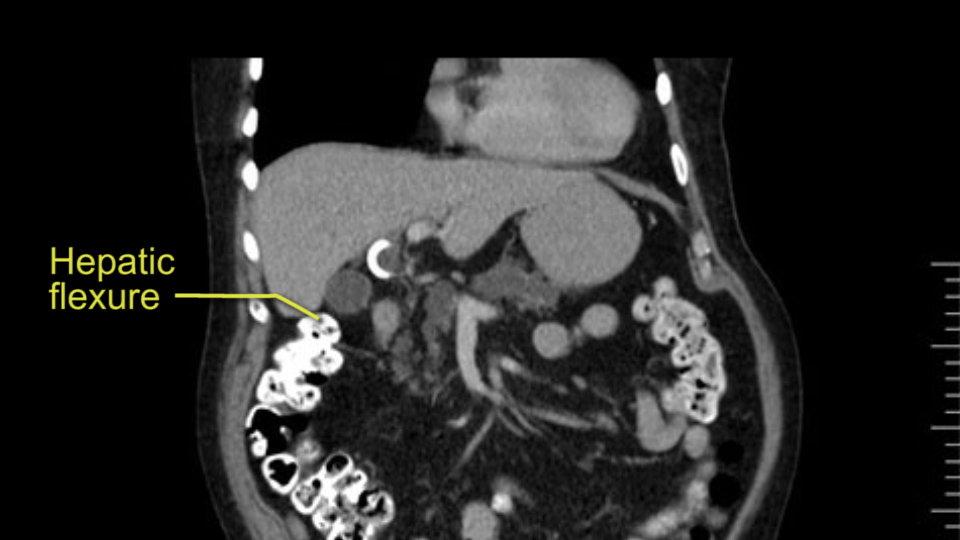

In planning for my further steps, the first key that I find, first do a gentle mobilization of the hepatic flexure of colon completely away because that’s going to help me do a good wide Kocher maneuver. Why do I slow down? Because there are small tributaries and small blood vessels which communicate between the transverse mesocolon and the head of the pancreas and you also have the loop of Henle all the blood vessels which drain into the superior mesenteric vein just as it gets underneath the neck of the pancreas.

The initial hepatic flexure mobilization and the Kocher procedure is then going to enable me to understand the uncinate process of this patient, which should not be a problem, again. But the initial pictures had shown a degree of touching. I would not even say involvement or abutment; a degree of touching with the superior mesenteric vein. So that would give me an early chance to assess how the superior mesenteric vein is in this patient. So this would be the initial slowing down moment.

The first steps of a pancreaticoduodenectomy involve ensuring the CT findings are correct: exploring for signs of metastatic disease, peritoneal implants involving the omentum or the undersurface of the diaphragm and if again this is confirmed exploration that there's no metastatic disease, I begin the mobilization and really determining the relationship of the tumor with the major visceral vessels. I start by an extended Kocher maneuver, identify the superior mesenteric vein below the neck of the pancreas. They’re very thin walled vessels and as you're dissecting you have to use the ultimate care and meticulously dissect the superior mesenteric vein, ligate the anterior branches and begin the dissection from below to under the neck of the pancreas. At this point, if there's no reason to be concerned about whether there is any vascular invasion below, I usually take the gallbladder down. I mobilize the common hepatic duct above the insertion of the gallbladder. This patients already has a stent in place. So I would divide the bile duct at this point. This facilitates the dissection of the anterior surface of the portal vein and as I would expect looking at this imaging that there is nothing to be concerned about in terms of vascular involvement.